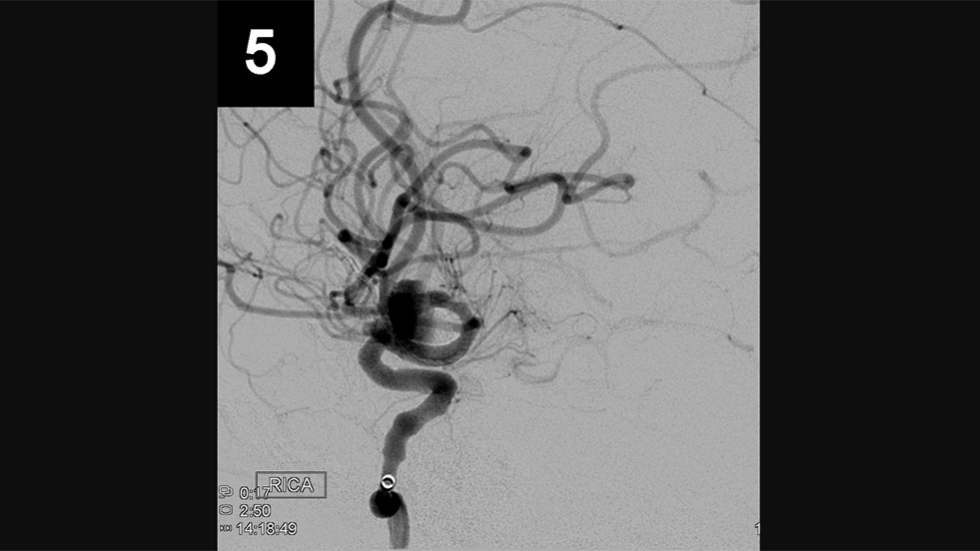

Primary Coil Embolization, Technique: Aneurysm

1 of 3

Primary Coil Embolization: Treats aneurysm from the inside rather than the outside. Fill aneurysm with embolic coils in order to obliterate blood flow.